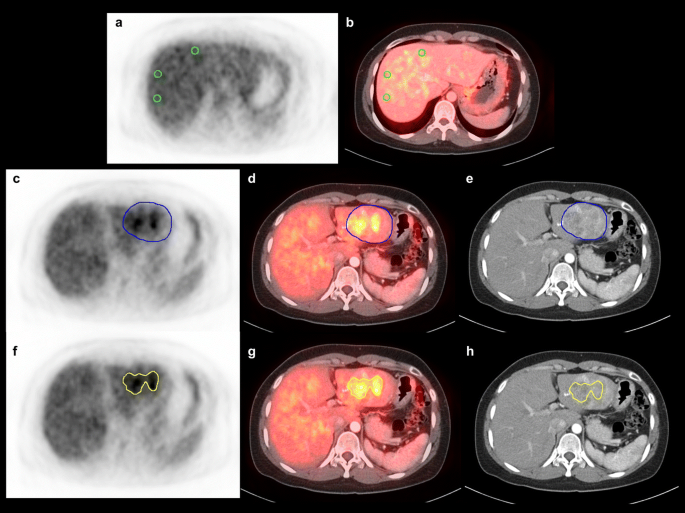

FDG PET/CT images of a 32-year-old woman with a single HCC showing an example of the measurement of MTV. PET and contrast-enhanced liver CT images were co-registered using a fusion module in viewer software. Three 1-cm-sized VOIs were drawn in the non-tumorous liver tissue on transxial FDG PET (a) and fused PET/CT images (b) and mean and standard deviation of SUV of non-tumorous liver tissue were measured. Afterwards, a VOI was drawn over the HCC lesion on FDG PET (c) and fused PET/CT images (d) along the rim of HCC lesion seen on the arterial or portal phase of contrast-enhanced CT images (e), and maximum and mean SUV of the HCC lesion were calculated. Voxels above an SUV of the 97.5th percentile of the non-tumorous liver tissue were automatically computed on FDG PET (f), fused PET/CT (g), and contrast-enhanced CT (h) images and the sum of volume of those voxels was calculated and defined as MTV. The present patient had a MTV of 22.2 cm3 and a TLG of 64.5 g and experienced intrahepatic recurrence 9.4 months after curative surgical resection. (GIF 467 kb)